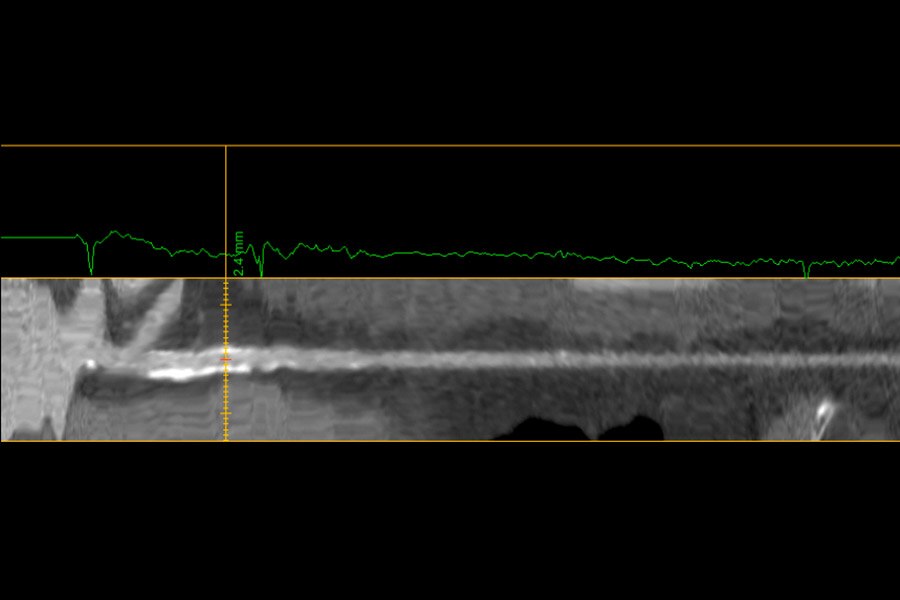

Visualization of the lumen of stents on 53-year-old male, 51 BPM, BMI 31